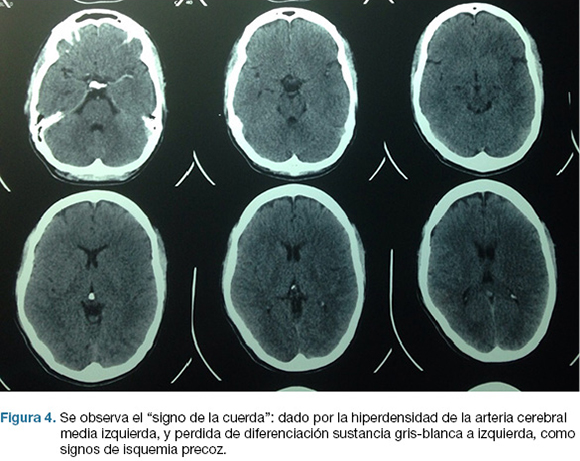

Se realiza TC de cráneo (Figura 4) y rTPA i/v. TC cráneo de control a las 24 hs sin cambios. A las 48 hs instala agravación del nivel de conciencia, apertura ocular al llamado, CGS: 9. Se repite TC cráneo (Figura 5), realizándose hemicraniectomía decompresiva de urgencia. En el post operatorio ingreso a CTI, IOT, en ARM, sin apertura ocular al llamado, gestos, localizando con miembro superior izquierdo. CGS: 8.